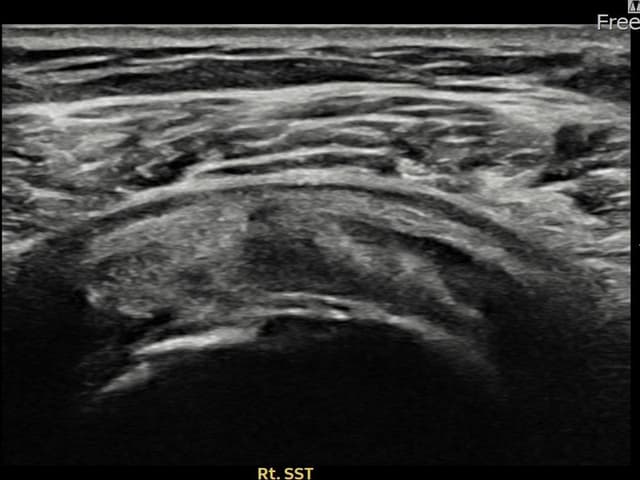

右侧 冈上肌腱 石灰化肌腱炎

14mm × 10mm